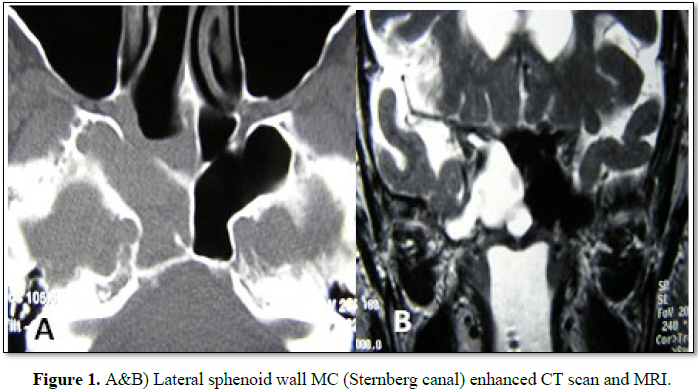

prior MC surgeries. In 2 cases the MC was located in the sphenoid lateral wall (Figures 1A and 1B), one was located in

the sphenoid roof (Figure 2), 2 in

the cribriform plate and one patient, with MEC diagnosis, had it located in the

frontal sinus. 66.6% had anterior rhinorrhoea (4/6) (Table 1).

The craniopharyngeal or Sternberg lateral canal is produced by the lack

of fusion of the ossifying points of the sphenoid sinus (between the greater

wings and the anterior sphenoid) during the embryonic period [2,3]. This

region, located posterolateral to the inferior wall of the sphenoid sinus, is

covered only by connective tissue, being the area of least resistance of the

skull base. This canal was described by Sternberg in 1888 for the first time 2

and is present until 3-4 years of age [4]. It is estimated that 0.1% to 4% of

adults have persistence of this canal [4]. In our series, three patients had MC

in the sphenoid sinus: one in the midline and two in the lateral wall.